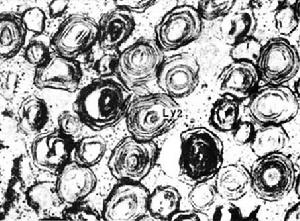

台-薩氏綜合徵(Tay-Sachs diesease):又叫黑蒙性家族痴呆症,溶酶體缺少氨基已糖酯酶A(β-N-hexosaminidase),導致神經節甘脂GM2積累(圖6-30),影響細胞功能,造成精神痴呆,2~6歲死亡。患者表現為漸進性失明、病呆和癱瘓,該病主要出現在猶太人群中。